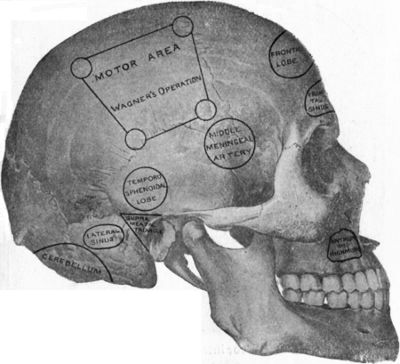

182.To illustrate the Site of Various Operations on the Skull337

186.Relations of the Middle Meningeal Artery and Lateral Sinus to the Surface as indicated by Chiene's Lines353